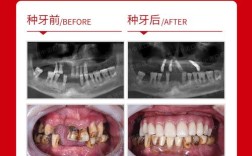

与传统种植牙相比,自体牙即拔即种在生物相容性、功能恢复和费用成本上具有显著优势,传统种植牙依赖钛等金属材料作为种植体,需经历骨整合期(3-6个月),而自体牙因含有活的牙周膜细胞,若处理得当,可实现“即刻负载”,缩短治疗周期;费用方面,自体牙即拔即种无需购买种植体,可降低30%-50%的经济负担,自体牙的形态、色泽与邻牙高度匹配,美学效果更自然。

术后感染是主要风险,需规范使用抗生素(如阿莫西林)7天;患者需保持口腔卫生,避免用患牙咀嚼硬物,长期预后方面,自体牙即拔即种的成功率约85%-95%,5年存活率与传统种植牙相当,但需定期复查监测牙根吸收情况(约10%-20%患者可能出现轻度吸收,通常不影响功能)。